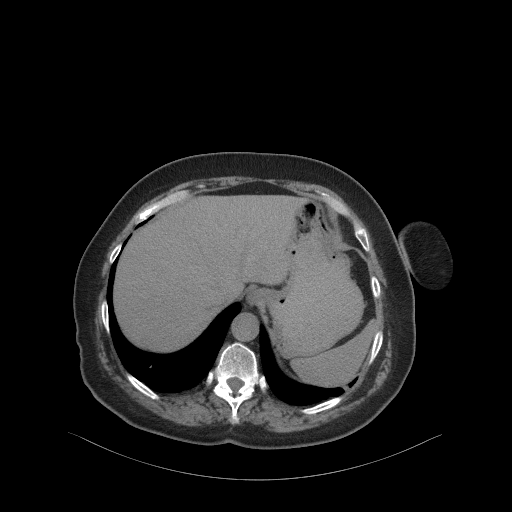

Generated VENOUS CT scan (AβB translation)

Full window (WL 1023.5, WW 4095 β Low β1024, High +3071)

Actual HU range: [-855.0, 775.1]

Lung window (WL -600, WW 1500 β Low β1350, High +150)

Actual HU range: [-855.0, 150.0]

Mediastinum window (WL 40, WW 400 β Low β160, High +240)

Actual HU range: [-160.0, 240.0]